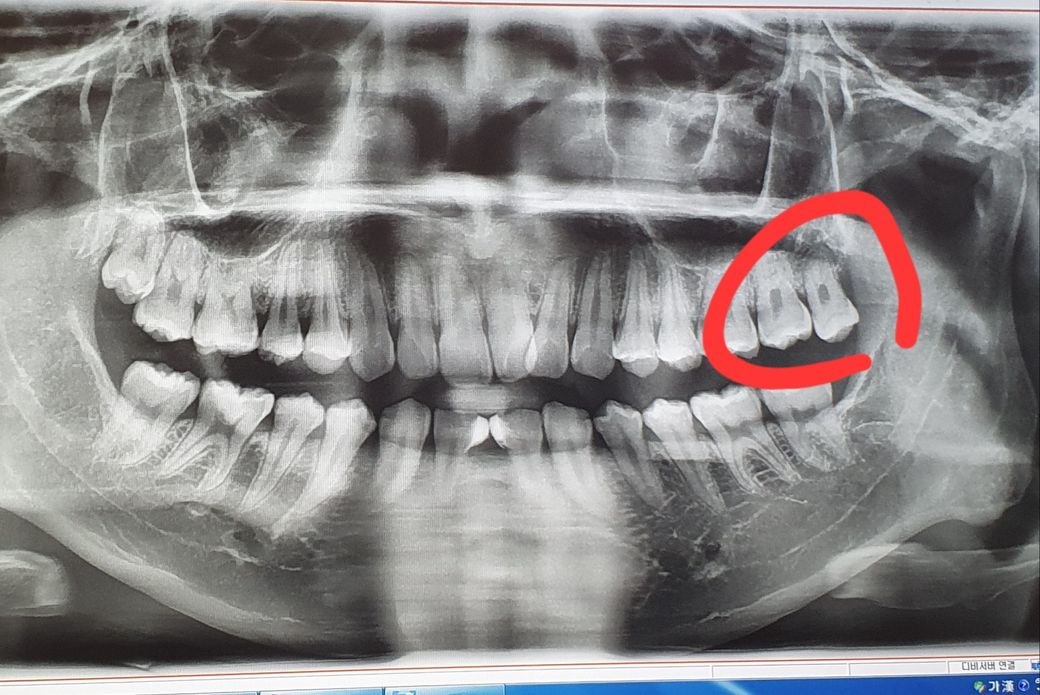

윗 사랑니 발치후 가래가 자주 나오는거 같은데 발치후 비염이 심해질수도 있나요?

(좌우반전이라 아마 빨간부분 말고 반대쪽이 오른쪽 윗사랑니 같아요.)

제가 오른쪽 윗사랑니가 잇몸에 묻혀있고 음식도 끼고 양치할때도 불편해서

의사 선생님 조언대로 발치를 했는데요.

• 1번 째 사진